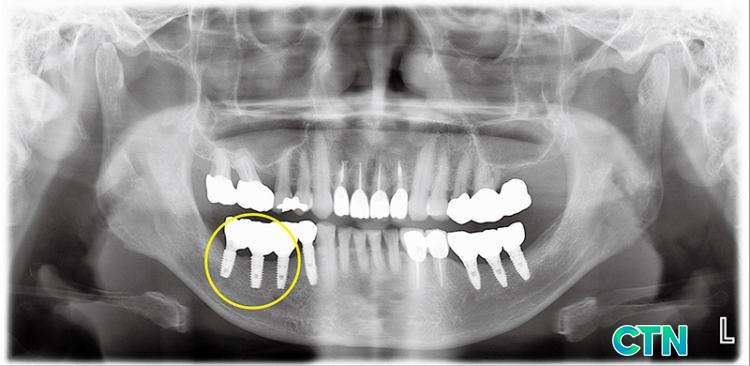

ڷ(1) ĸ 3 öƮ ֺ ٰ ġ ȯڴ. ʾƷ öƮ ֺ Ǵµ, ̴ öƮ ֺǻ ǹѴ. ո Ȯ ä öƮ ĸϿ Ұ 3 öƮ ǥ Ǹ鼭 ǰ ֺ ȴ. ٷ ʿ ° öƮ ֺδ ϰ ǰ , ̰ ο ̾ ȴ. ᱹ öƮ ϰ 3 ո ̿ β ٷ ̽ Ͽ. ̽ĵ ֺո з Ͽ Ǵ ϱ ݼӸ ̿Ͽ , 6 ݼӸ öƮ ĸߴ. (2) öƮ ĸ ϼ ¿ Կ ij.